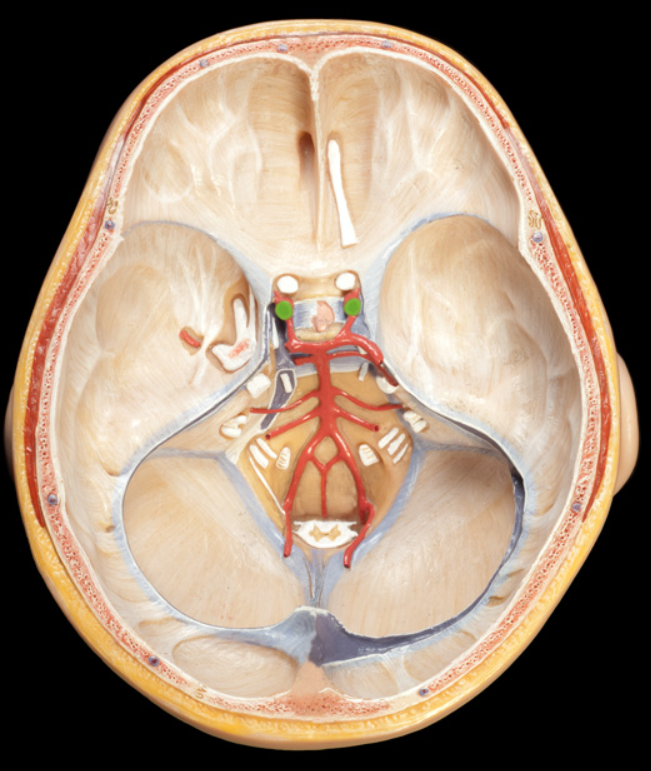

falx cerebri

falx cerebelli

tentorium cerebelli

dural sinus

vertebral arteries

New cards

Basilar artery

10

New cards

internal carotid arteries

11

New cards

Arterial circle